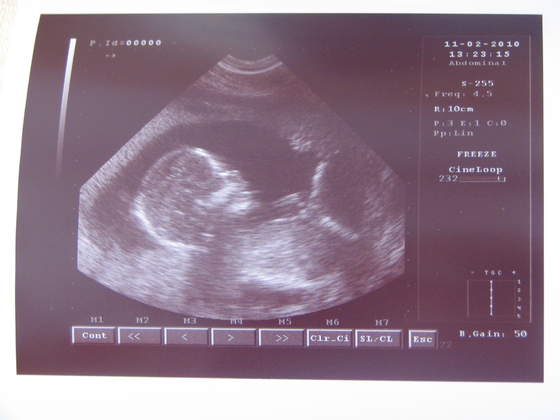

Dziewczyny, oto mój "Facet", wg wczorajszego USG

Zdjęcia, mam nadzieję, wyraźne... Skaner mi się popsuł, pozostało mi tylko zrobić "zdjęcie ze zdjęcia" :-)

lekarz powiedział, że na 100% to chłopczyk?No rewelacja!!!!!!!!!!!!!!!

Boski ten Twój facet,lekarz powiedział, że na 100% to chłopczyk?

Powiedziałam, że oczywiście. A on powiedział, że chlopak